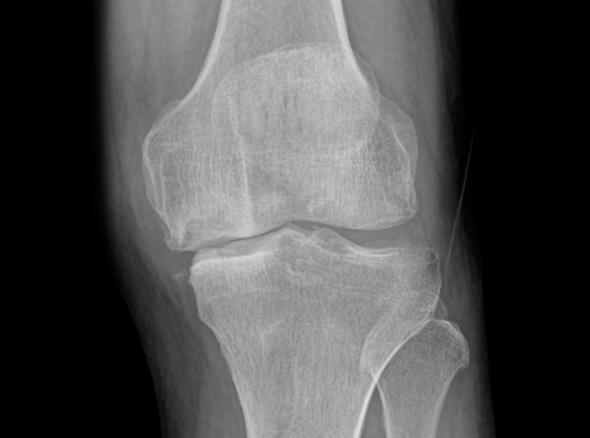

퇴행성관절염은 치료의 시기가 매우 중요합니다.

한번 진행이 시작되면 피하기가 어려워 치료가 빠를수록 진행을 최대한 늦출 수 있습니다.

인공관절 수술은 진행이 악화되어 더 이상 약물로 치료할 수 없을 때 시행하는 최후의 방법입니다.

초기에는 수술이 아닌 비수술 치료만으로 생활에 불편함이 없도록

통증을 완화시키고 증상을 충분히 완화시킬 수 있습니다.

중기에는 비수술치료를 진행하고, 증상이 악화되는 경우 정상 조직을 최대한 보존하고 병변부위만 선택적으로 수술하는 관절내시경을 진행하게 됩니다.

말기의 퇴행성 관절염 환자에게 인공관절 수술은 최후의 수단으로 시행됩니다.